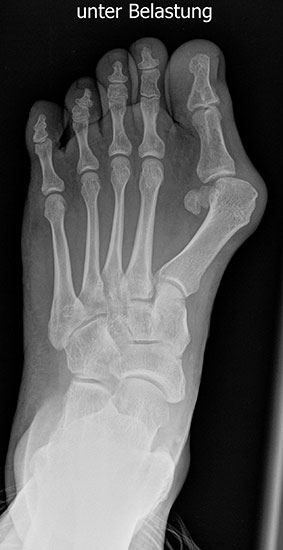

Bei einem juvenilen Hallux valgus handelt es sich um eine schon im Kindes – oder Adoleszentenalter 1 bestehende Valgusdeviation der großen Zehe bei Spreizfuß mit vergrößertem Intermetatarsalwinkel I / II aufgrund einer Adductionsstelllung des Metatarsale I – Metatarsaus primus varus.

Im Gegensatz zum Hallux valgus des Erwachsenen ist die Valgusabweichung der großen Zehe meist geringer ausgeprägt als bei Erwachsenen, der Intermetatarsalwinkel oft stark vergrößert. Die Angaben ab wann der Intermetatarsalwinkel als vergrößert gilt schwanken zwischen > 9° 2 und >14°3. Das Ausmaß der Beschwerden korrelieren nicht mit dem Auftreten und dem Schweregrad der Deformität (Zollinger 1990, Zollinger 1993). Begünstigend wirkt eine Schrägstellung des ersten Tarsometatasalgelenkes (Hefti 1998) und eine Hypermobilität dieses Gelenkes 2 in Kombination mit einer Bindegewebsschwäche. Häufig liegt eine positive Familienanamnese vor. In einer Untersuchung von Coughlin fand sich eine Vererbung über die mütterliche Linie in 72%, ein milder bis stark ausgeprägter Knick-Senkfuß in 17% (das entspricht der Quote von Knick-Senkfüßen in der Normalbevöl­kerung) aber in 22% ein Pes adductus, das ist wesentlich mehr als in der Normalbevölkerung zu erwarten wäre 4. Auch für Hefti (1998) gilt der Pes adductus als Komponente des Sichelfußes als begünstigend. Zur Inzidenz des Hallux valgus juvenilis finden sich je nach Autor verschiedene Angaben. Nach Auswertung von Schuluntersuchungen liegt die Häufigkeit zwischen 1,6 % bis 17% 56. Häufig tritt die Fehlstellung doppelseitig auf. Der Anteil der betroffenen Mädchen liegt 4-5x höher als bei Jungen (Lamprecht 2015).

Standard ist die belastete Röntgenaufnahme des Fußes dorso-plantar und seitlich. Günstig ist eine Röhrenkippung von 10°-20°, um die Gelenke der Lisfranc-Linie einsehen zu können.

Ergänzend kann eine Schrägaufnahme hilfreich sein. Bei Metatarsalgien oder Pathologien der Sesambeine liefert die Sprinteraufnahme zusätzliche Informationen. Bei einer Pes planovalgus Fehlstellung wird ergänzend ein Saltzman view durchgeführt.